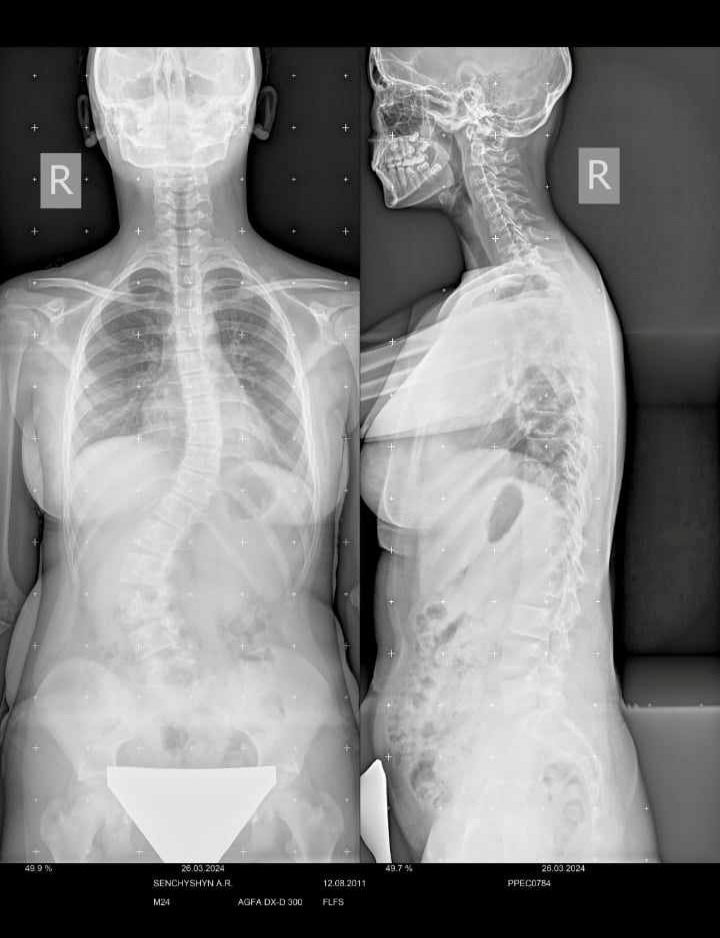

- У дівчини виявили аномалію Кіарі – вроджене захворювання мозку, а також важку форму сколіозу.

Окрім аномалії Кіарі, лікарі діагностували в 12-річної доньки тернопільського захисника сколіоз третього ступеня. Зі слів мами, наразі кутовий нахил становить 54 градуси. Через це у поперековому відділі хребет відійшов від осі на 3,5 сантиметри.

— Як пояснили лікарі, у спину Ангеліни будуть вкручувати спеціальні металеві конструкції, що підтримуватимуть її поставу. Загалом, без цієї операції нам не обійтися, — наголошує мама дівчинки.